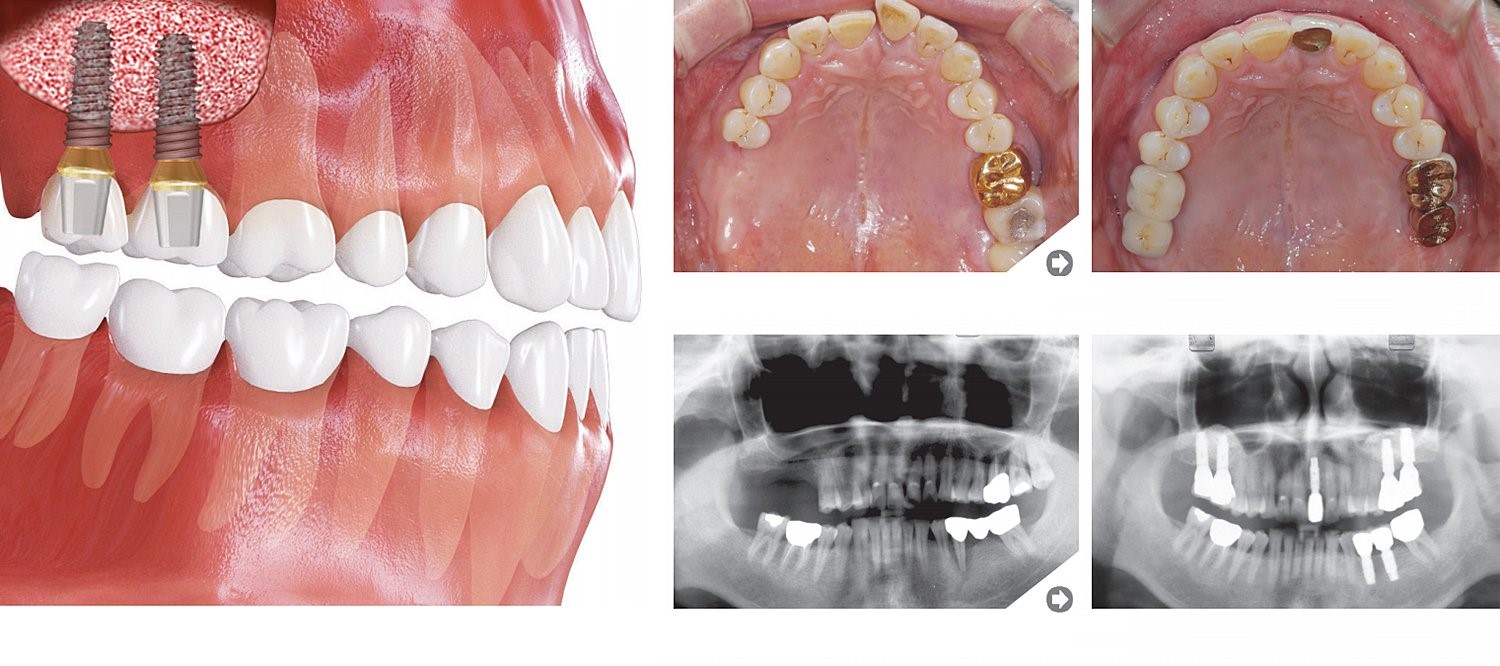

Trūkst pāris zobu

Augšējie molāri